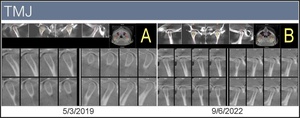

Clearly Michelle’s symptoms improved subjectively as reported by the patient, and objectively using data. With orthotropic and orthodontic treatments, we were able to alleviate life altering symptoms and improve not only her TMJ function and facial symmetry but her airway symptoms as well. The patient states her favorite part was no surgery, no pain, and minimal interruption of her daily life. Moreover, these anatomical orthotics not only provide a temporary stable occlusion, but also support the optimal position of the TM joints day and night. See Figure 9.

The CBCT scans before and after treatment show the intrusion of the mandible in the airway due to Michelle’s TMD before treatment. With Myoaligner® and her additional therapies in what could have been 18 months long treatment (treatment interruption by COVID), she had a dramatic improvement in airway volume. See Figure 10.